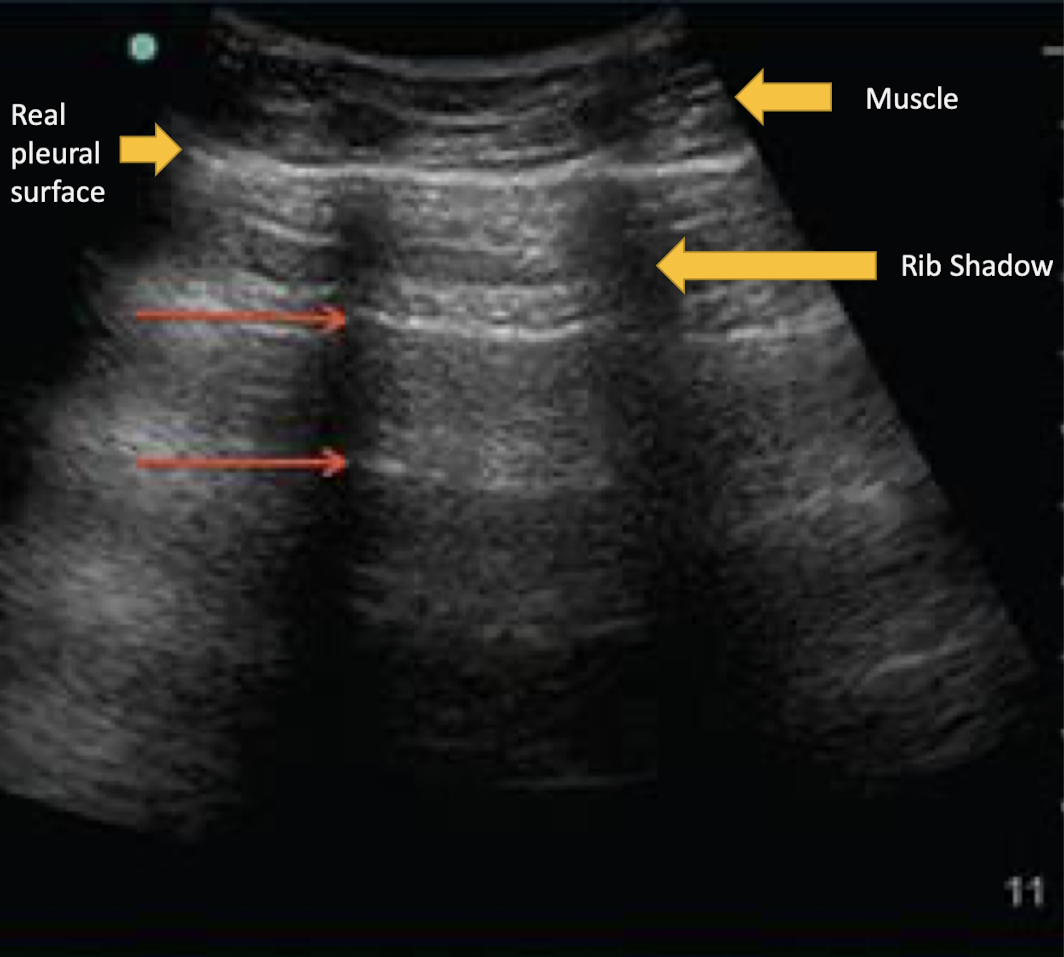

cannot see below a structure that reflects back all waves

acoustic shadow

What artifact is this showing?